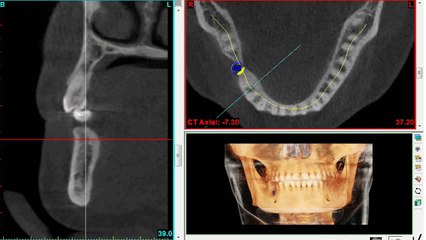

How to Prevent Gum Infection Disease and Dental Implant Infection| Ask at Partha Dental Specialist.br Follow post-operative instructions. Pre-emptive prescription of antibiotics for some days prior to surgery can help reduce the risk of implant infection. Daily cleaning of all the surfaces above and below the gumline is critical to preventing peri-implant disease. Know more about Dental Implants @ ...